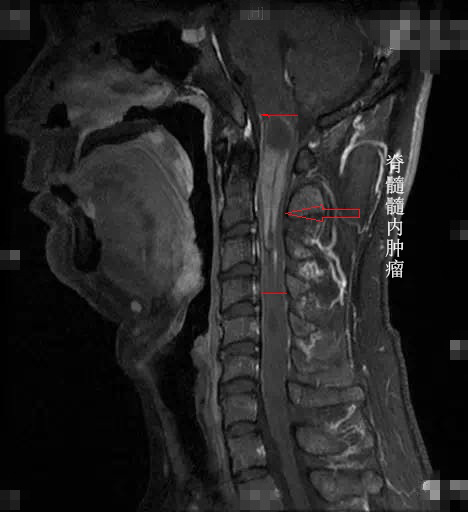

图为患者小智术前的核磁影像,箭头所指为脊髓髓内肿瘤

从人体的后脑到颈部一直向下延伸到尾椎,是一根长长的管道,里面是一根手指粗细的脊髓,它就像一根“电缆”,里面布满了导线一样的神经,大脑通过这根“电缆”下达指令,并接收来自身体各个部位的信号。而延颈髓肿瘤,上端濒临脑干,下端延伸几公分甚至几十公分,挤压正常的脊髓,导致神经传导出现了严重问题,患者因此出现无力、莫名的疼痛甚至瘫痪的症状。“延髓是生命中枢,相当于总闸,牵一发动全身。”王贵怀说。